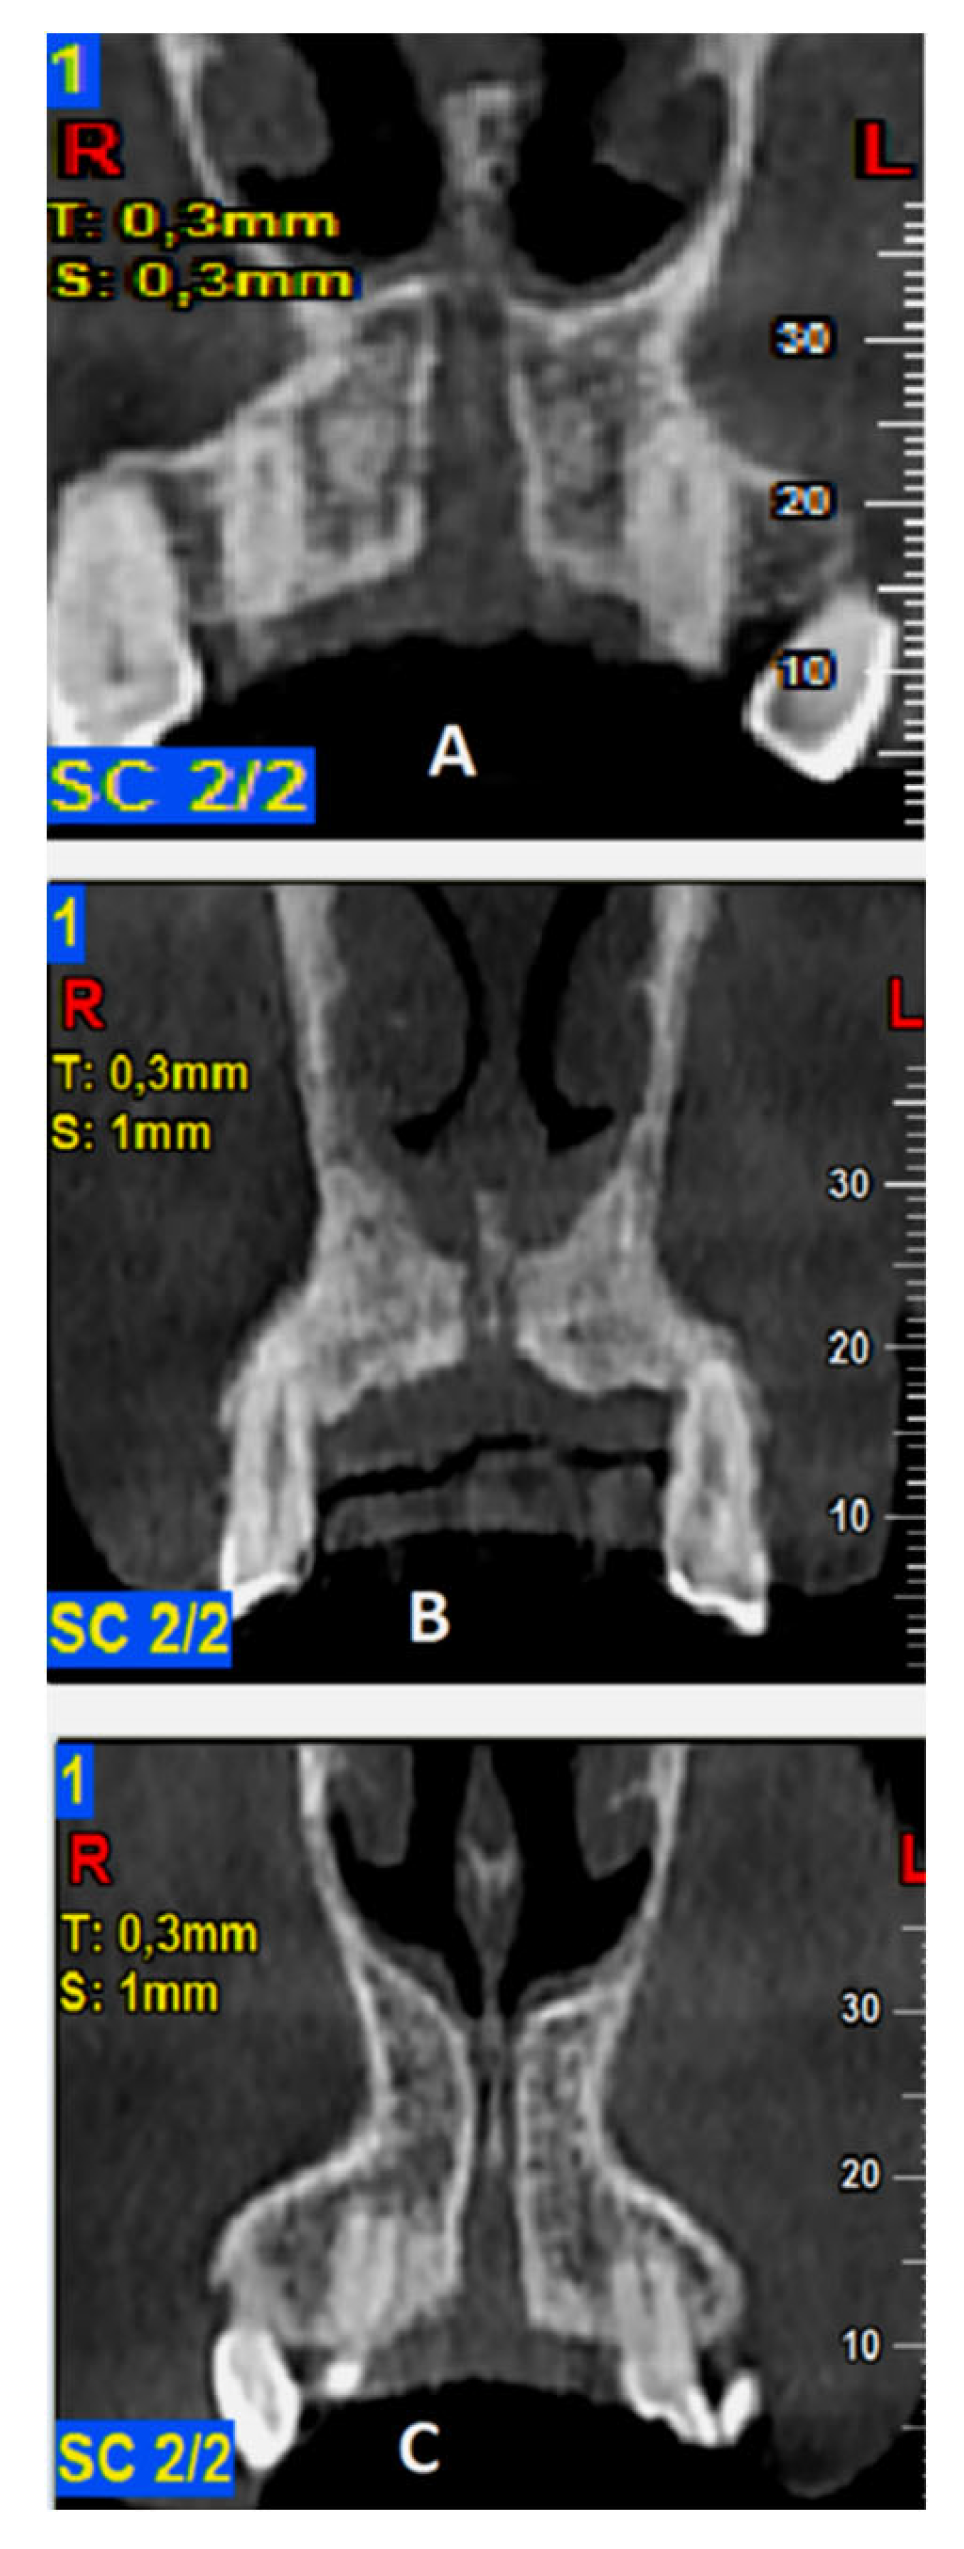

The required measurements (in mm) were: (#1) the diameter of IF, (#2) the diameter of SF, (#3) the diameter in the middle of the NPC, (#4) the total length of the NPC, (#5) the crestal distance from the buccal border of the IF to the facial aspect of the BOP, (#6) the distance midway from the buccal bone wall of the NPC to the facial aspect of the bone wall, using a horizontal line from the palatal border of the IF, and (#7) the most cranial distance from the buccal border in the middle of the NPC to the facial aspect of the buccal bone wall. These were measured on the reconstructed sagittal CBCT images (Figure 1 and Figure 2). All measurements were performed using the manufacturer’s specialized computer software (NNT v.6.2, Verona, Italy) [6,27,28]. Anatomical types of NPC were also recorded and classified as: a single canal (A), two parallel canals (B), variations of the Y-type of canal with one IF and two or more SF (C). This was performed on the reconstructed coronal CBCT images (Figure 3) [6,27,28].

Figure 3.

Classification of anatomic types of the nasopalatine canal (NPC) as evaluated in coronal cone beam computed tomography (CBCT) images: (A)—a single canal, (B)—two parallel canals, (C)—variations of the Y-type of canal with one incisive foramen (IF) and two or more Stenson foramen (SF).

Evaluation of the different anatomic types of NPC resulted in the detection of a single canal in 56.5%, two separate parallel canals in 25%, and variations of the Y-type canal in 18.5% of the scans, respectively (Figure 3). The descriptive analysis of NPC dimensional evaluation parameters is presented in Table 1.

In the same vein, the standardized projection protocol we used allowed us to also assess the different anatomic types of the NPC. In this manner, a single canal was detected in 56.5%, two separate parallel canals in 25%, and Y-type variations of the canal were observed in 18.5% of the evaluated CBCT scans. Our findings were in accordance with those of other studies [6,14,27], while Bornstein et al. (2011) reported that in the most cases a single canal was present [6,14]. In addition, NPC types had a significant effect on SF and mid-NPC diameters [measurement #3 (p = 0.040)], with mean values generally higher for the type C variant. The total length of the NPC showed higher mean values for the type A NPC. In the Bornstein et al. (2011) study of 100 subjects using CBCT, it was reported that the type of NPC had a significant effect only on IF diameter, with mean values highest for type A, followed by type B and C variants in a descending order [6].